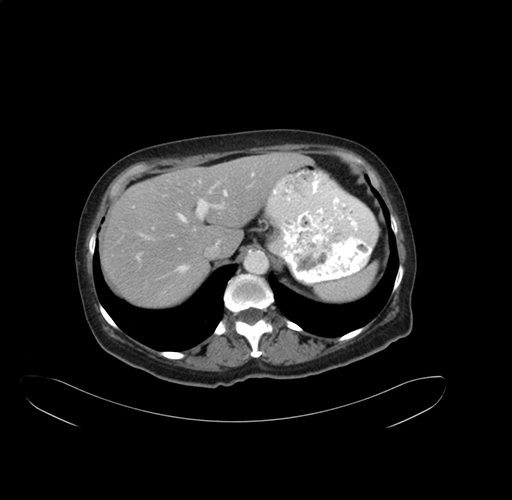

Axial Venous